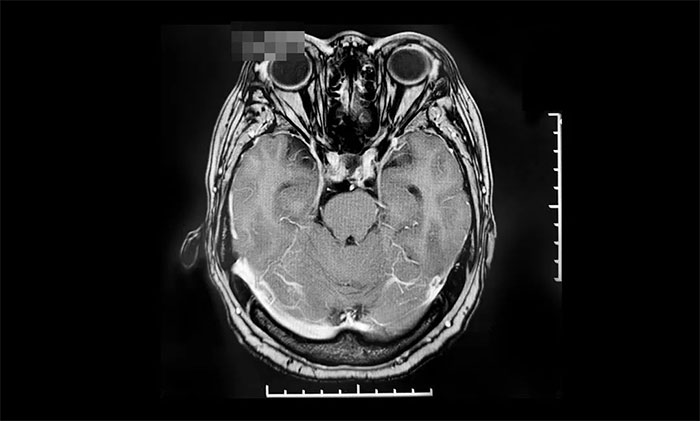

▲ 肿瘤复发后,来我院行伽玛刀治疗前影像

2022年8月,因视力下降就医,复查提示肿瘤复发,遂来上海蓝十字脑科医院进行伽玛刀治疗,后顺利出院。今年10月,患者来院复查,影像学检查提示肿瘤体积较治疗前明显缩小,患者视力较前改善,控制良好,陈琦主任叮嘱其继续随访观察。

▲ 出院14个月后复查影像